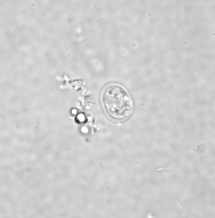

Professor: Dr. Glena Fe A. Yapchulay-Alcabasa

ENTAMOEBA HISTOLYTICA CYST